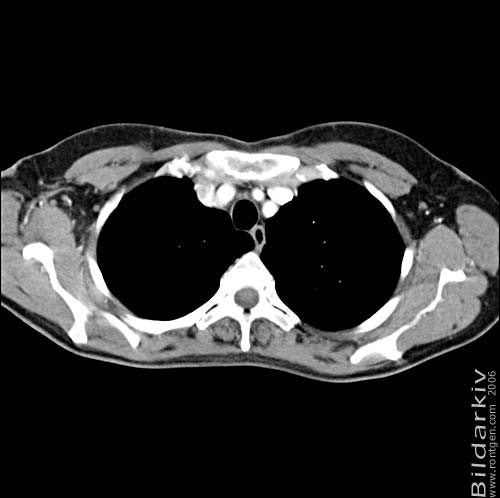

Thorax 12

Snitt över thorax med kontrast. Sk. mediastinum-fönstersättning.

Mediastinum